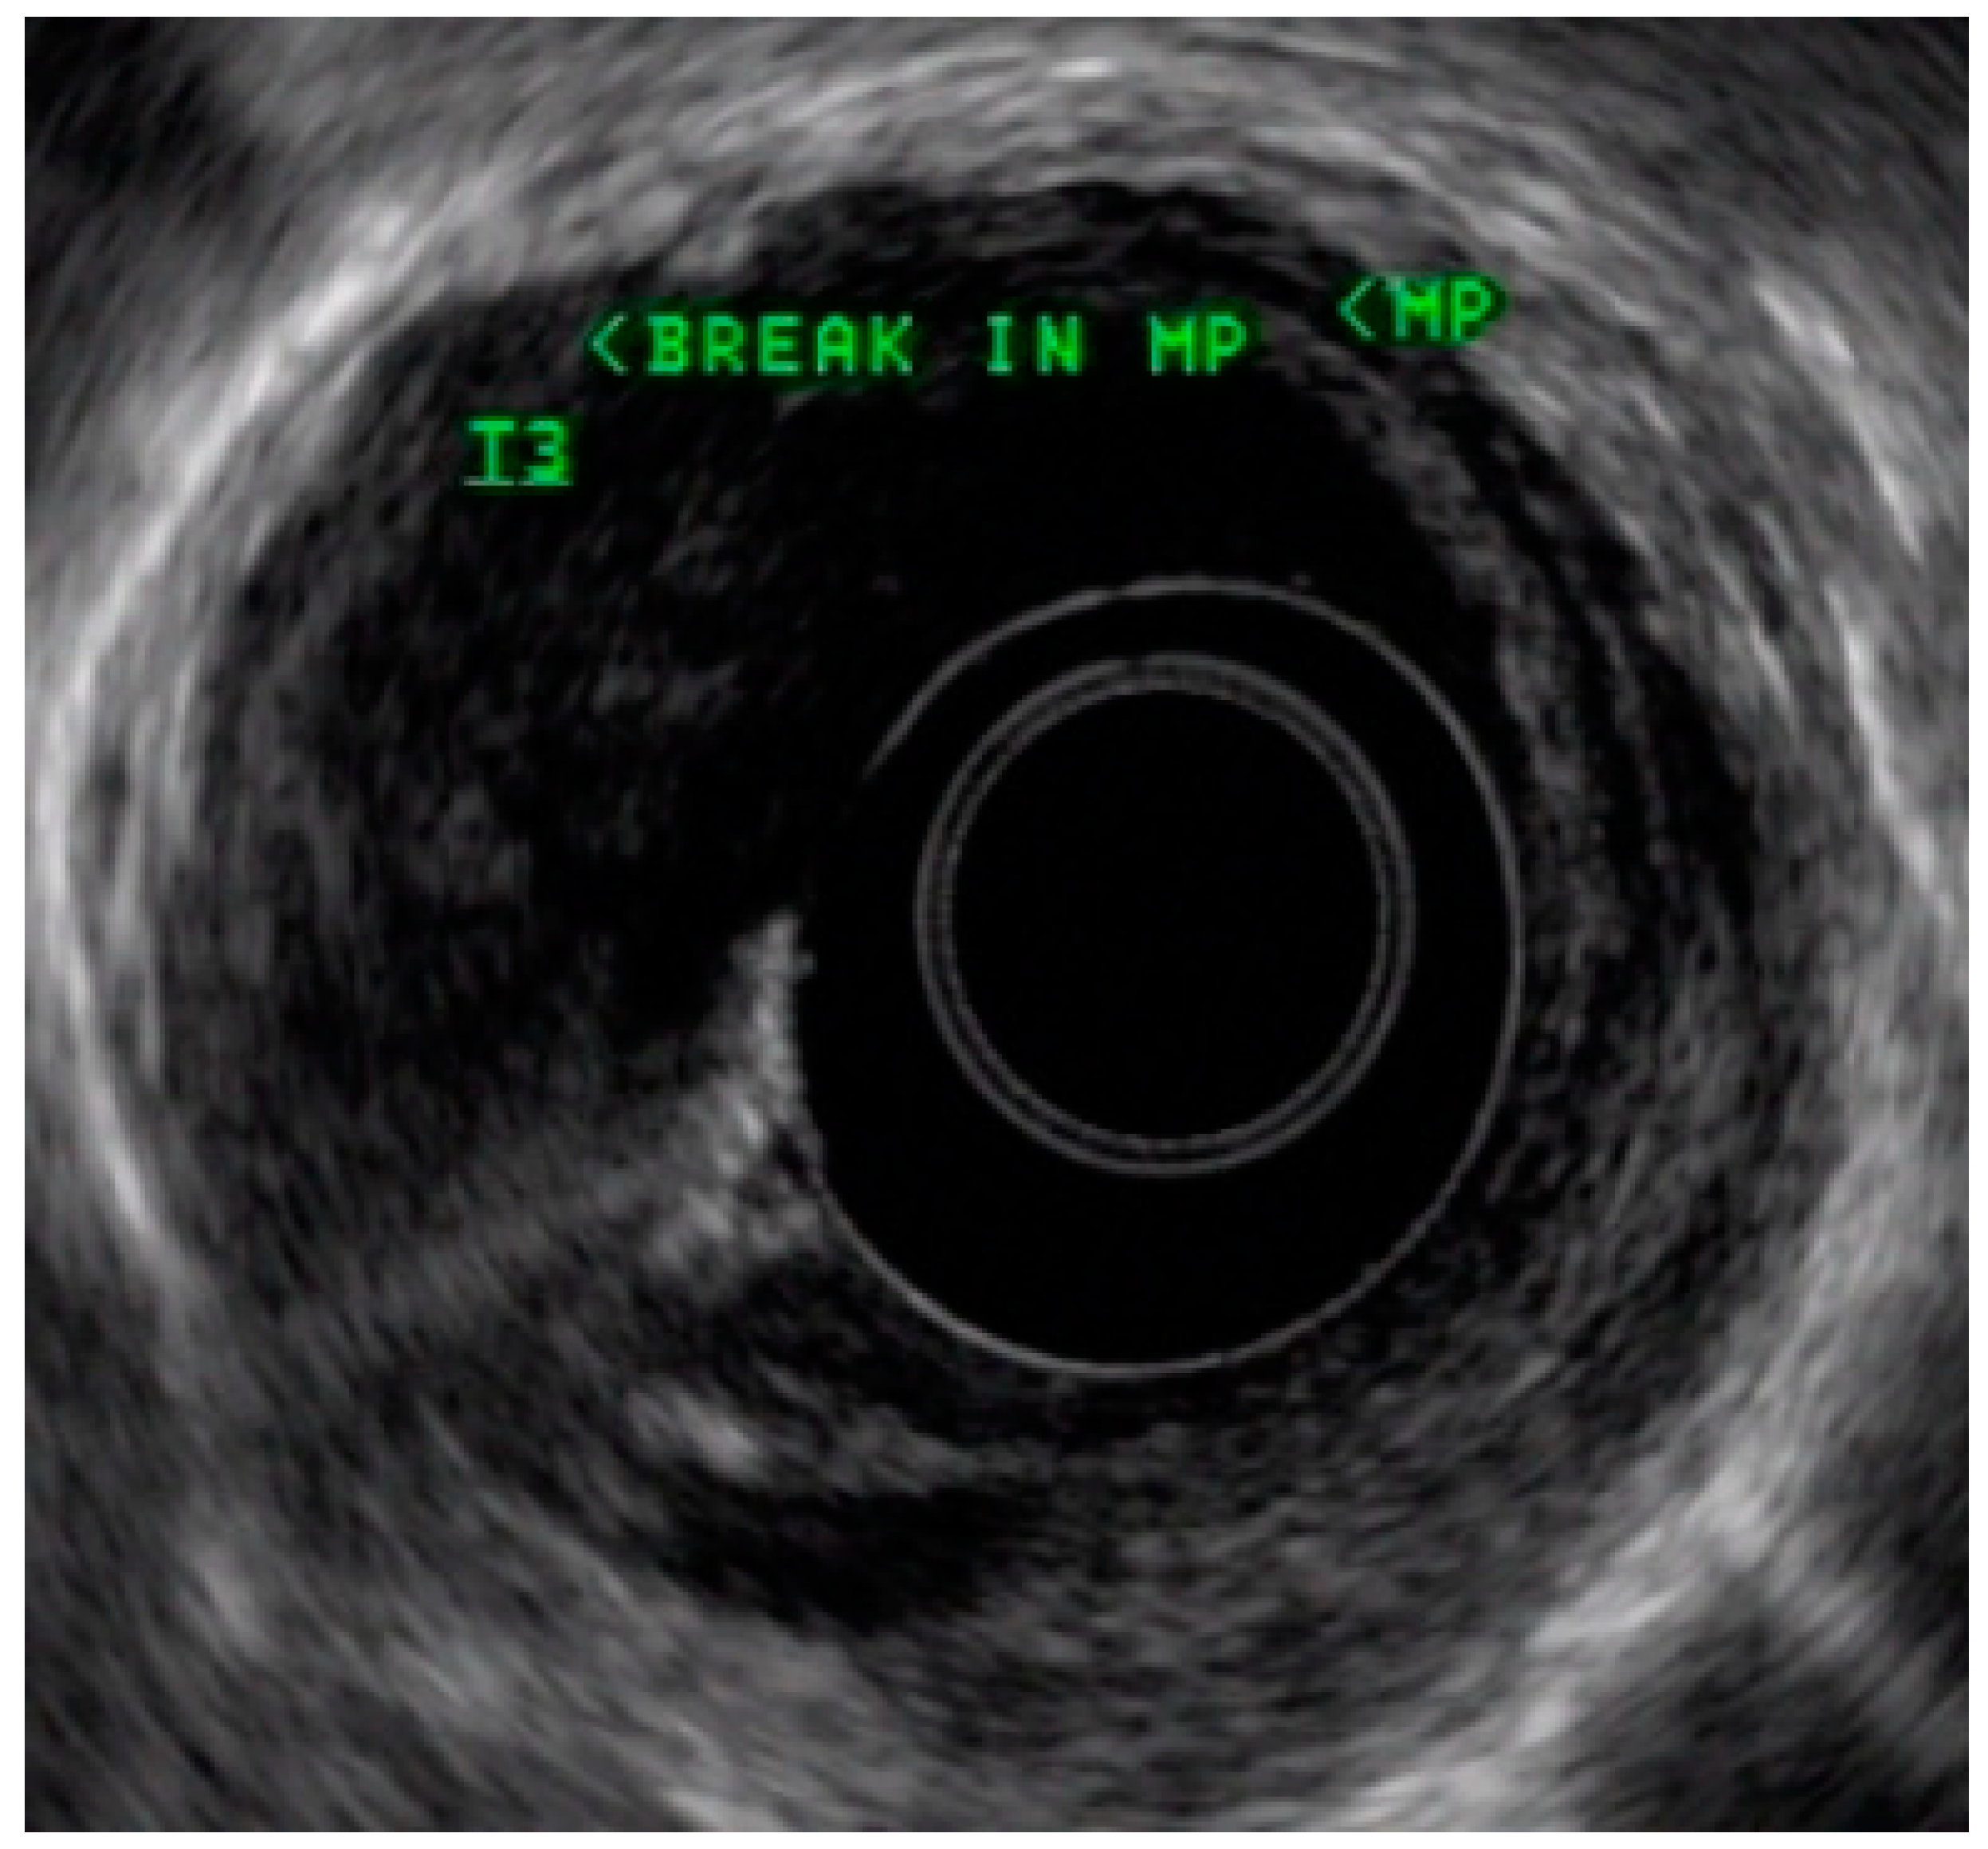

4.3. Endoscopic Ultrasound in Staging of Gastric Cancer

- Spolverato, G.; Ejaz, A.; Kim, Y.; Squires, M.H.; Poultsides, G.A.; Fields, R.C.; Schmidt, C.; Weber, S.M.; Votanopoulos, K.; Maithel, S.K.; et al. Use of Endoscopic Ultrasound in the Preoperative Staging of Gastric Cancer: A Multi-Institutional Study of the US Gastric Cancer Collaborative. J. Am. Coll. Surg. 2015, 220, 48–56. [Google Scholar] [CrossRef] [PubMed]

- Mocellin, S.; Pasquali, S. Diagnostic accuracy of endoscopic ultrasonography (EUS) for the preoperative locoregional staging of primary gastric cancer. Cochrane Database Syst. Rev. 2015, 2015, CD009944. [Google Scholar] [CrossRef]